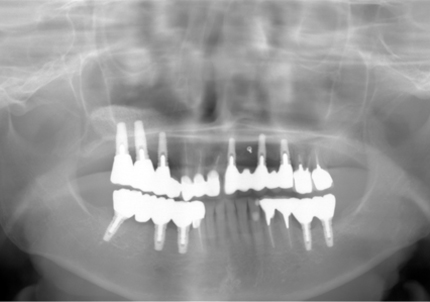

↑ 2007年6月30日(初診)

↑2006年4月24日

↑2006年4月24日(初診時)

2015年6月初診時レントゲン